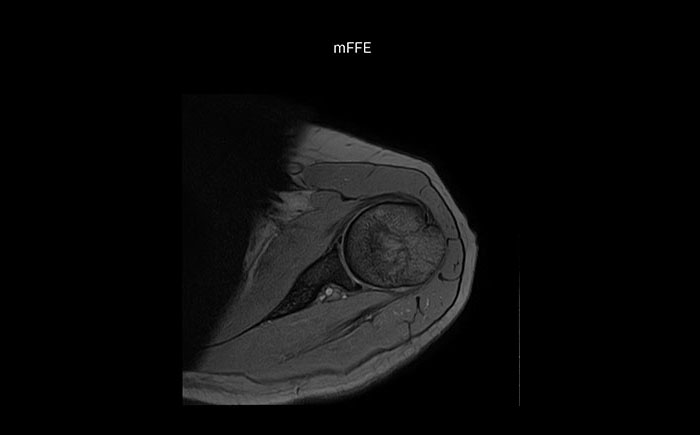

Die Prodiva Schulterspule ist sehr flexibel und hat eine grosse Abdeckung; dies erleichtert eine gute Positionierung, was wiederum zur ausgezeichneten Bildqualität und hohem SNR beiträgt, die wir in unseren Schulteruntersuchungen erreichen.

Scandauer: 2:55 Minuten, FOV: 160 mm, erfasste Voxel: 0,55 x 0,83 x 3,0 mm.

Scandauer: 04:19 Minuten, FOV: 160 mm, erfasste Voxel: 0,55 x 0,80 x 3,0 mm.

Scandauer: 02:50 Minuten, FOV: 160 mm, erfasste Voxel: 0,70 x 0,99 x 3,0 mm.